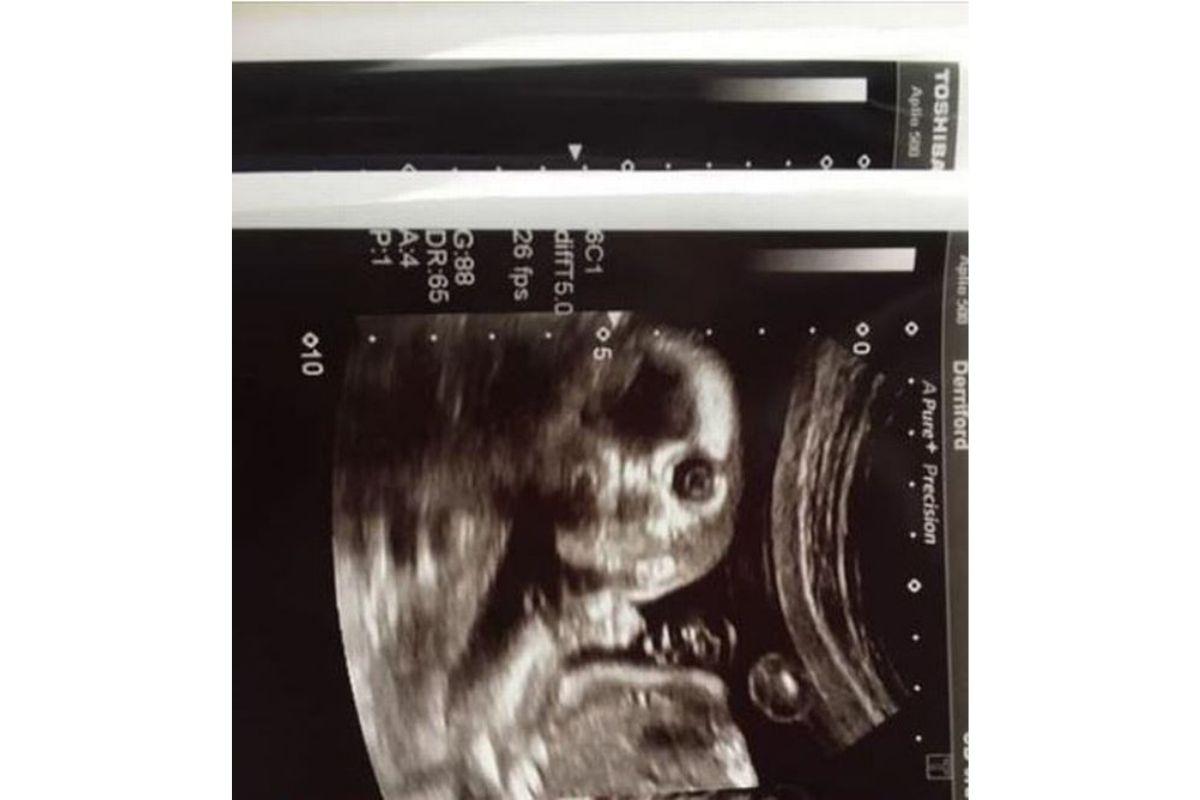

Joanne Greer, de 34 anos, deu um susto em todo mundo quando foi fazer um ultrassom de rotina às 20 semanas de gestação. Até a própria parteira ficou surpresa, afinal, a criança encarou a câmera e o momento foi registrado pelo hospital Plymouth, no Reino Unido.

De acordo com o jornal local Plymouth Live, a mãe contou sobre como tudo aconteceu: “Todos nós vimos as fotos padrão e fofas de lado, mas essa é nossa. É tão engraçado que quase nos molhamos de rir. A parteira riu e disse: ‘Isso não acontece com frequência”.

Em declaração, a família afirmou que usará a imagem na festa de 18 anos do aniversário do bebê, que ainda não teve o sexo revelado, pois a mãe decidiu saber apenas após o parto. “Acho que ninguém viu uma imagem digitalizada assim antes. Definitivamente, colocarei essa foto no cartão de aniversário de 18 anos da criança”, concluiu.